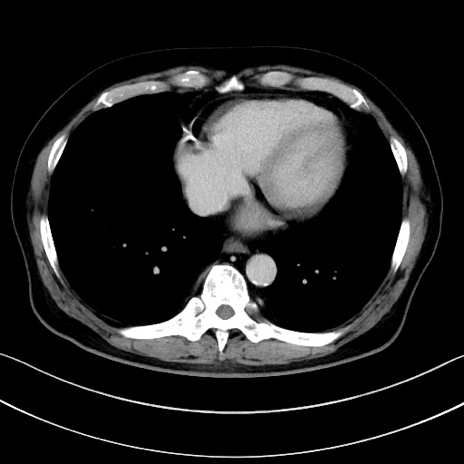

症例15(横断像)

【症例】70歳代男性

【主訴】腹痛

【現病歴】今朝から腹痛あり。全体的に痛い。特に左上の方。排ガスが今日はない。冷や汗が出る。

【既往歴】直腸癌術後

【身体所見】左側腹部〜上腹部に圧痛あり。腹膜刺激症状明らかなではない。軽度反跳痛。左下腹部に術後瘢痕あり。

【データ】WBC 7700、CRP 0.02